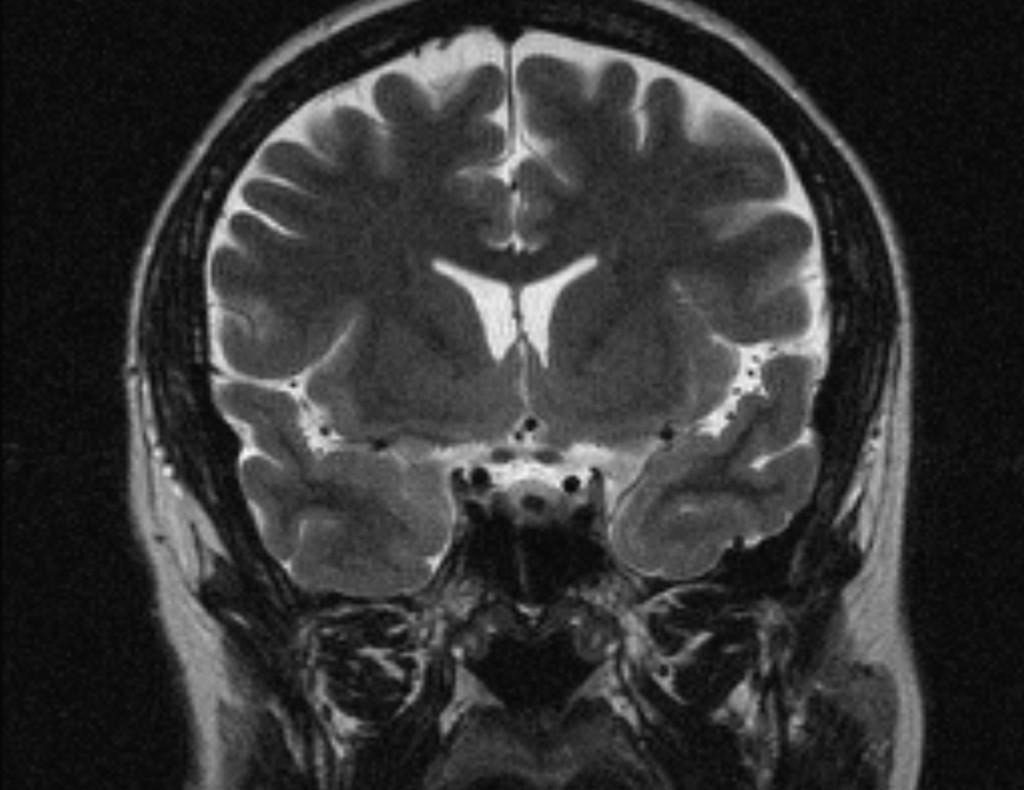

Иллюстрации и пояснения: гиподенсивный очаг на КТ головного мозга